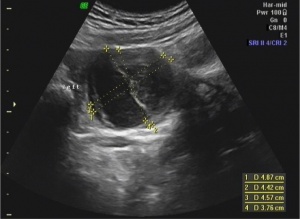

File:double_bleb_sign.jpg|Double bleb sign (yolk sac and amniotic cavity | |||

- Double bleb sign

- Yolk sac and amniotic cavity that look like two bubbles within gestational sac

- Yolk Sac